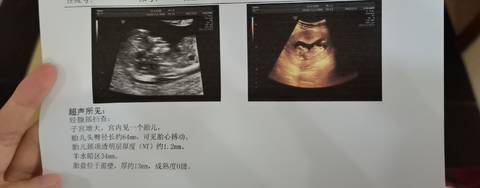

nt通过,12周+????????一胎纯属好奇,帮我看看是佩奇还是乔治哈哈哈

journal_insert_pic_1681861180